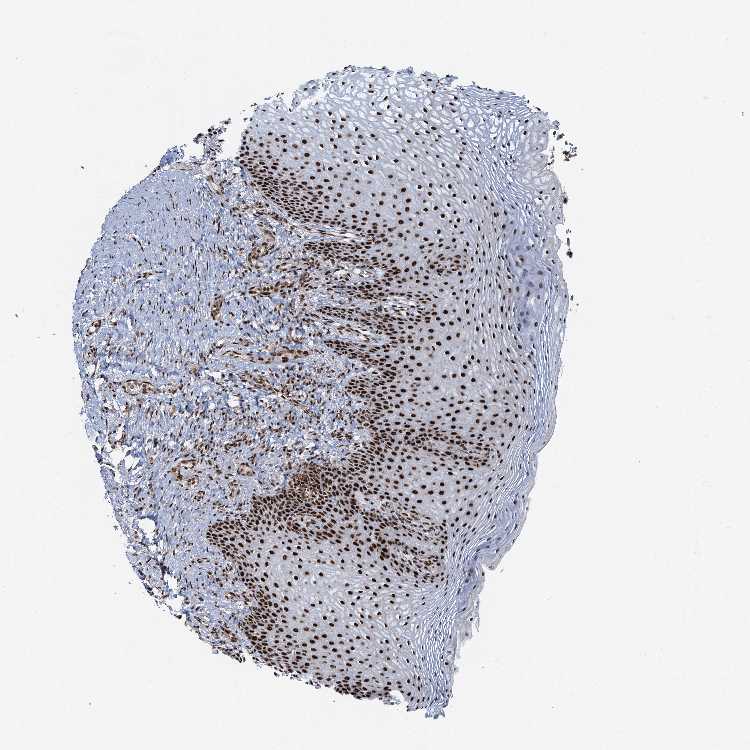

VAGINA - Antibody stainingi

Antibody staining in the annotated cell types in the current human tissue is reported as not detected, low, medium, or high, based on conventional immunohistochemistry profiling in selected tissues. This score is based on the combination of the staining intensity and fraction of stained cells.

Each image is clickable and will lead to virtual microscopy that enables deeper exploration of all samples and also displays staining intensity scores, fraction scores and subcellular localization as well as patient and tissue information for each sample.

Antibody HPA040252

Squamous epithelial cells High